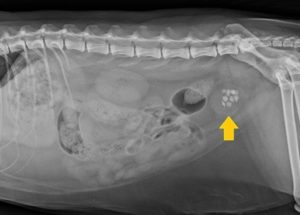

Кроме того, назначается рентгенография брюшной полости питомца и ультразвуковое исследование почек для получения информации об их структуре, виде, размеров и количества камней.

- Вместе с тем необходимо провести контрастную рентгенографию, которая укажет на расположение образований.

- Параллельно следует осуществить ультразвуковое исследование брюшной полости, чтобы оценить состояние почек, мочевого пузыря, а также подтвердит или опровергнет наличие фосфатов или уратов, их количество и размеры.

Проведя ряд исследований, в число которых обязательно входит УЗИ и два вида рентгена, включая контрастный, ветврач ставит диагноз и определяет нужную методику. Лечение мочекаменной болезни у кошек может быть консервативным или хирургическим.